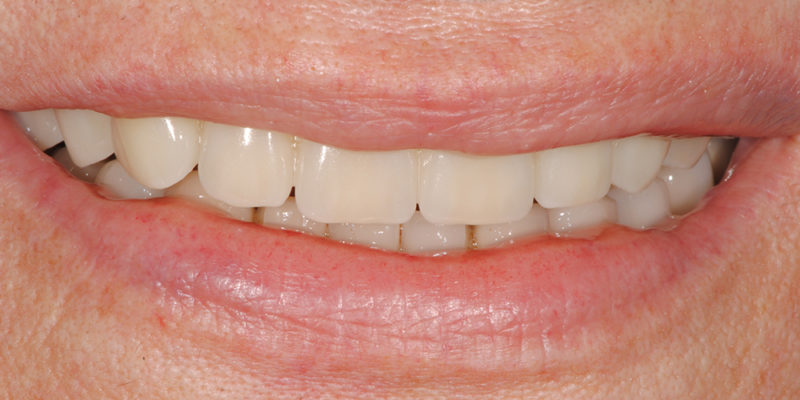

Ripristino dell'arcata superiore atrofica su impianti con ricostruzione estetica in zirconia e ceramica Category: Lavori ImpiantiMaggio 9, 2018Condividi questo ProgettoShare with FacebookShare with TwitterShare with Google+Share with PinterestShare with LinkedInProject navigationPreviousPrevious project:Ripristino dell’arcata superiore atroficaNextNext project:Ripristino dell’arcata superiore ed inferiore